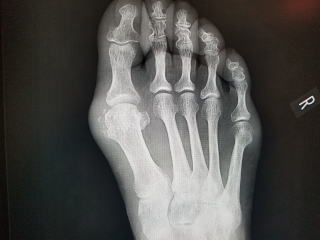

痛風は血中の尿酸が増えて関節に析出して炎症を起こします。尿酸は水に溶けにくく特に温度が下がる足の母趾関節(MTP関節)に発症しやすいです。肘関節、膝関節、アキレス腱などで起こることもあります。

偽痛風は関節内にピロリン酸カルシウム水和物の結晶が沈着する病気です。原因ははっきりしていません。特定の病気に合併することがあります。レントゲンで白い沈殿が写ります。

ピロリン酸カルシウム沈着症は、関節軟骨内に沈着し時として関節内に放出され炎症反応を起こし発症します。高齢者に発症し、レントゲンで関節内に石灰沈着を認めます。急激に発症することが多く、変形性関節症や化膿性関節症などを鑑別を要します。

検査所見として、硝子軟骨内に線状の高エコー像(痛風は軟骨表面に高エコー)。X線で軟骨内石灰化。CRP高値、赤沈亢進。関節液は黄白色に混濁し、顕微鏡検査でピロリン酸カルシウムの結晶を認めます。

レントゲンで点状もしくは線状の軟骨内石灰化+顕微鏡で平行六面体の結晶 2点が揃えば確定、一点のみは推定